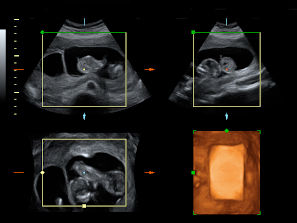

Ecografía Embarazo 4D Semana 12 - ANOMALÍAS CROMOSÓMICAS